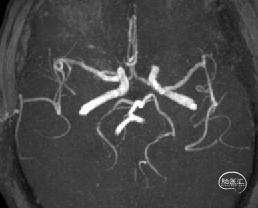

术后影像学检查

术后72小时MRA:右侧大脑中动脉血流复通,双侧血管对称。